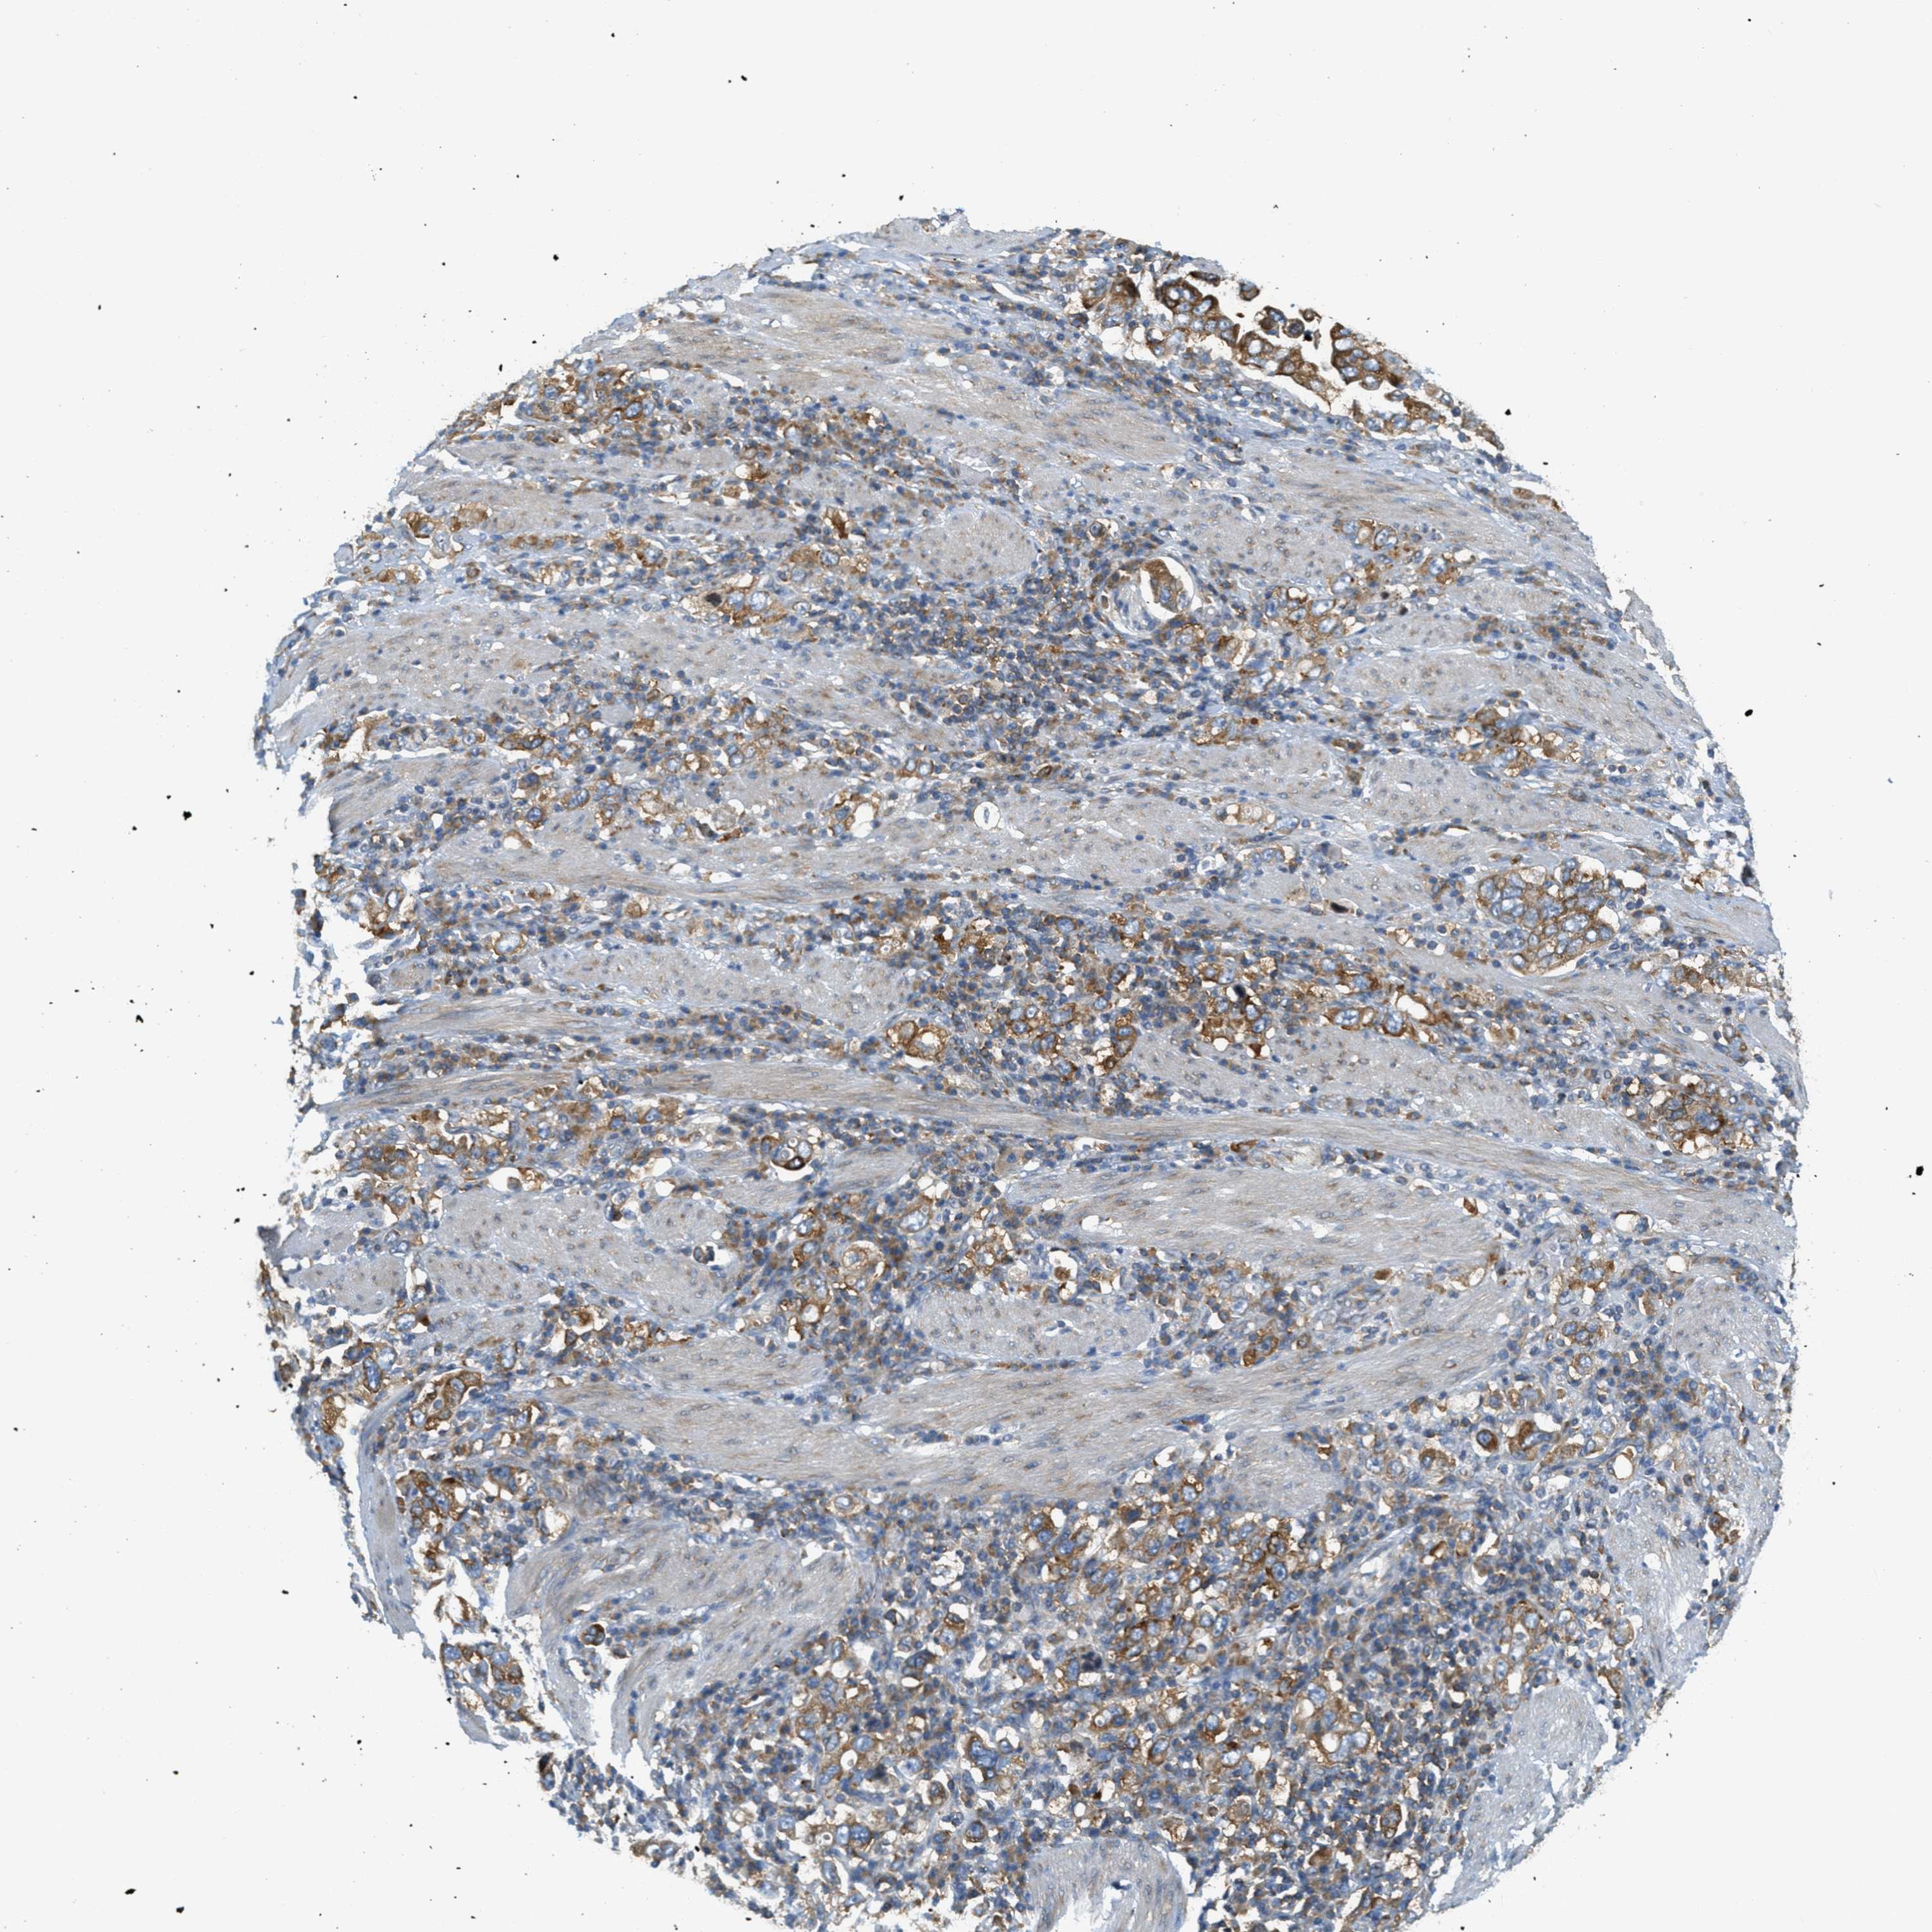

STOMACH CANCER - Protein expressioni

A mouse-over function shows sample information and annotation data. Click on an image to view it in a full screen mode. Samples can be filtered based on level of antibody staining by selecting one or several of the following categories: high, medium, low and not detected. The assay and annotation is described here.

Antibody stainingi

Antibody staining in the annotated cell types in the current human tissue is reported as not detected, low, medium, or high, based on conventional immunohistochemistry profiling in selected tissues. This score is based on the combination of the staining intensity and fraction of stained cells.

Each image is clickable and will lead to virtual microscopy that enables deeper exploration of all samples and also displays staining intensity scores, fraction scores and subcellular localization as well as patient and tissue information for each sample.

Antibody HPA017578

Staining

High

Medium

Low

Not detected

Intensity

Strong

Moderate

Weak

Negative

Quantity

>75%

75%-25%

<25%

None

Location

Nuclear

Cytoplasmic/membranous

Cytoplasmic/membranous,nuclear

Adenocarcinoma, NOS